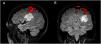

ObjetivoSe muestran 4 casos valorando la utilidad de la resonancia magnética funcional en el estudio prequirúrgico de pacientes con tumores neuroepiteliales disembrionarios. Para la obtención de imágenes se utilizó un equipo de resonancia magnética Philipps Intera de 3.0 Tesla y la técnica Blood Oxygenation Level-Dependent, permitiendo localizar las áreas elocuentes de lenguaje y motora mediante la aplicación de paradigmas específicos.

ResultadosEn un caso el tumor se encontraba adyacente al área de Broca, en 2 casos coincidía con Wernicke, en un paciente estaba menos de 1cm del área motora de la mano y en otro próximo a la memoria. Solo 2 de los pacientes fueron operados, no produciéndose déficit funcional postoperatorio. Se observó activación hemisférica contralateral al tumor sugestivo de neuroplasticidad en uno de los pacientes.

ObjectiveThis work aims to assess the usefulness of functional magnetic resonance imaging (fMRI) in the preoperative study in four patients with DNET. A Philips Intera 3.0 Tesla magnetic resonance imaging scanner and the Blood-Oxygen-Level-Dependent (BOLD) technique were used to obtain the images, making it possible to locate the eloquent areas for language and motor areas through the application of specific paradigms.

ResultsIn one case the tumour was adjacent to Broca's area, in two cases it coincided with Wernicke's area, in one patient it was<1cm from the motor area for the hand and in another close to memory. Only two of the patients were operated on, without postoperative functional deficit. Hemispheric activation contralateral to the tumour suggestive of neuroplasticity was observed in one of the patients.